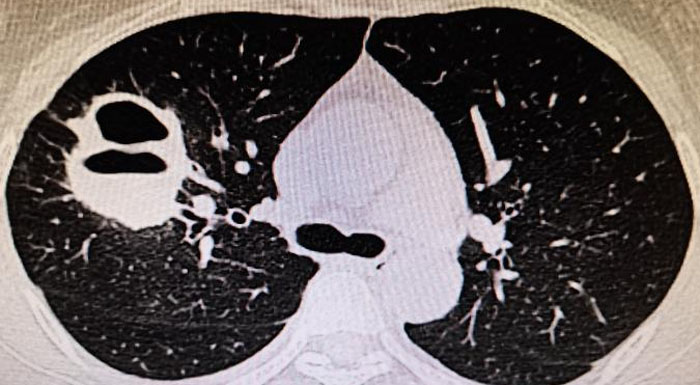

9、當肺CT出現如下情況,這可能是ANCA相關性血管肺部表現。